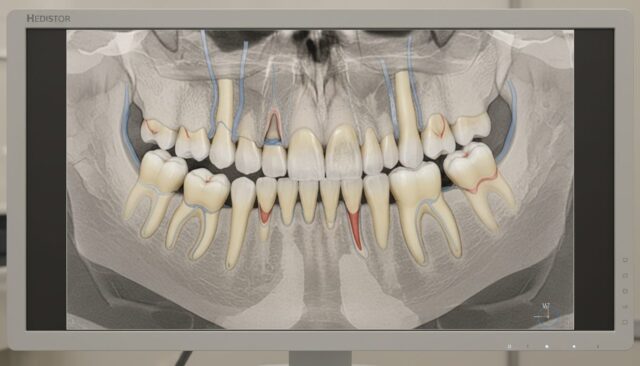

歯科用CTによる精密診断

親知らずの抜歯を検討する際、最も重要なのは正確な診断です。

当院では歯科用CTを活用した精密診断により、親知らずの位置や神経との距離を立体的に把握します。これにより安全性を確認したうえで治療計画を立てることができます。

親知らずの根っこが下顎の神経に近い場合などは、CT撮影を行わせていただくことがあります。より安全に親知らずを抜歯処置するための精密な診査・診断を行っております。